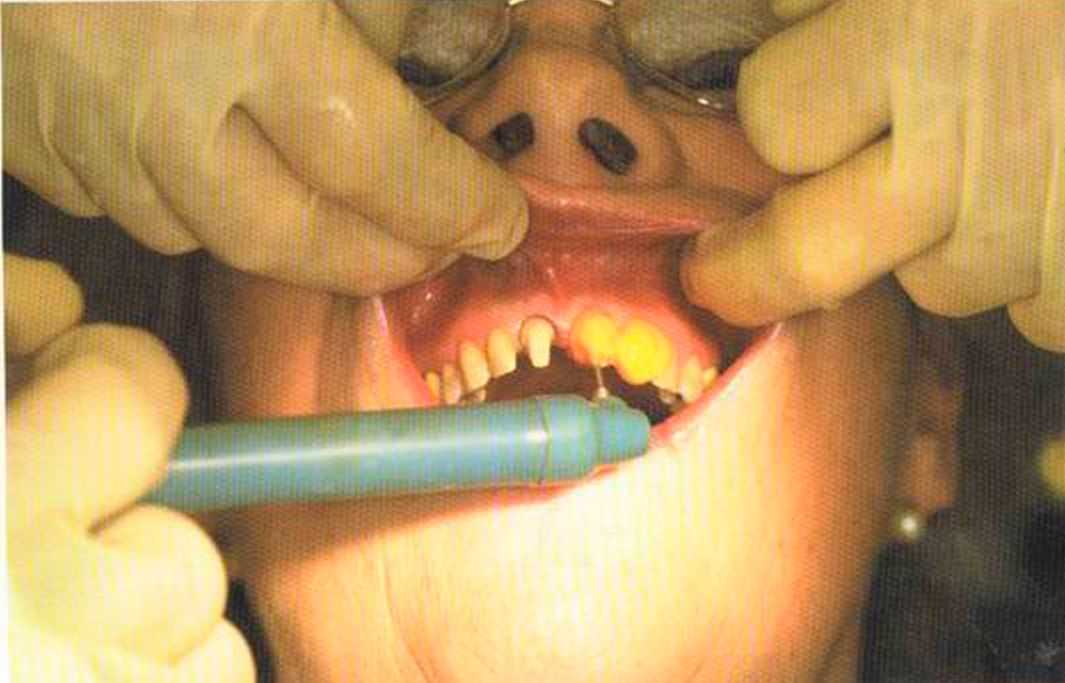

Доктор Лангханке фиксирует вкладки.

Присутствие техника, выполнившего работу, при фиксации коронок в полости рта — хорошее подспорье для доктора. Сведения о проблемах или трудностях, которые возникли и были решены при изготовлении реставрации (например, путь введения), являются полезной и важной информацией для врача.

Часто забывают упомянуть о важности работы ассистента. Но если была допущена ошибка при подготовке керамической вкладки, всё придется делать сначала.

Только что зацементированная работа в полости рта. Цементирование керамических вкладок осуществлено на цемент двойного отверждения Vivadent, а коронок ln-Сегат на Panavia ТС.